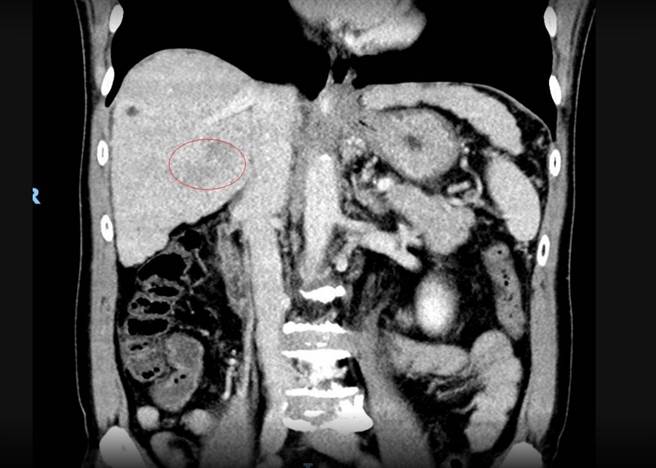

53岁的詹姓男子轻忽B肝,10多年未追踪竟已是晚期肝癌,肿瘤10公分。(彰化医院提供/吴敏菁彰化传真)

彰化医院肿瘤中心主任宋时雨表示,詹男是B肝患者,因为没症状就没有追踪,直至今年中觉得肚子胀胀、闷闷的,查发现其右肝部位出现10公分大的肿瘤,并已经扩散到肝门静脉,诊断为3B期。